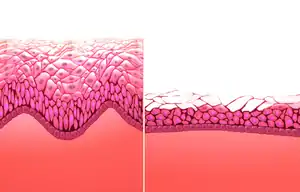

Human vagina; normal canal (left) and canal during menopause (right) | |

The epithelium of the ectocervix (the portion the uterine cervix extending into the vagina) is an extension of, and shares a border with, the vaginal epithelium.[36] The vaginal epithelium is made up of layers of cells, including the basal cells, the parabasal cells, the superficial squamous flat cells, and the intermediate cells.[37] The basal layer of the epithelium is the most mitotically active and reproduces new cells.[38] The superficial cells shed continuously and basal cells replace them.[10][39][40] Estrogen induces the intermediate and superficial cells to fill with glycogen.[40][41] Cells from the lower basal layer transition from active metabolic activity to death (apoptosis). In these mid-layers of the epithelia, the cells begin to lose their mitochondria and other organelles.[38][42] The cells retain a usually high level of glycogen compared to other epithelial tissue in the body.[38]

Under the influence of maternal estrogen, the vagina of a newborn is lined by thick stratified squamous epithelium (or mucosa) for two to four weeks after birth. Between then to puberty, the epithelium remains thin with only a few layers of cuboidal cells without glycogen.[40][43] The epithelium also has few rugae and is red in color before puberty.[4] When puberty begins, the mucosa thickens and again becomes stratified squamous epithelium with glycogen containing cells, under the influence of the girl's rising estrogen levels.[40] Finally, the epithelium thins out from menopause onward and eventually ceases to contain glycogen, because of the lack of estrogen.[10][39][44]

Keratinization happens when the epithelium is exposed to the dry external atmosphere.[10] In abnormal circumstances, such as in pelvic organ prolapse, the mucosa may be exposed to air, becoming dry and keratinized.[46]

After menopause, the body produces less estrogen. This causes atrophic vaginitis (thinning and inflammation of the vaginal walls),[39][150] which can lead to vaginal itching, burning, bleeding, soreness, or vaginal dryness (a decrease in lubrication).[151] Vaginal dryness can cause discomfort on its own or discomfort or pain during sexual intercourse.[151][152] Hot flashes are also characteristic of menopause.[118][153] Menopause also affects the composition of vaginal support structures. The vascular structures become fewer with advancing age.[154] Specific collagens become altered in composition and ratios. It is thought that the weakening of the support structures of the vagina is due to the physiological changes in this connective tissue.[155]